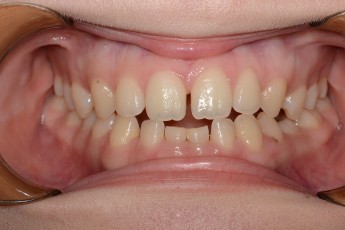

Before & After

- 덧니교정

Before

After